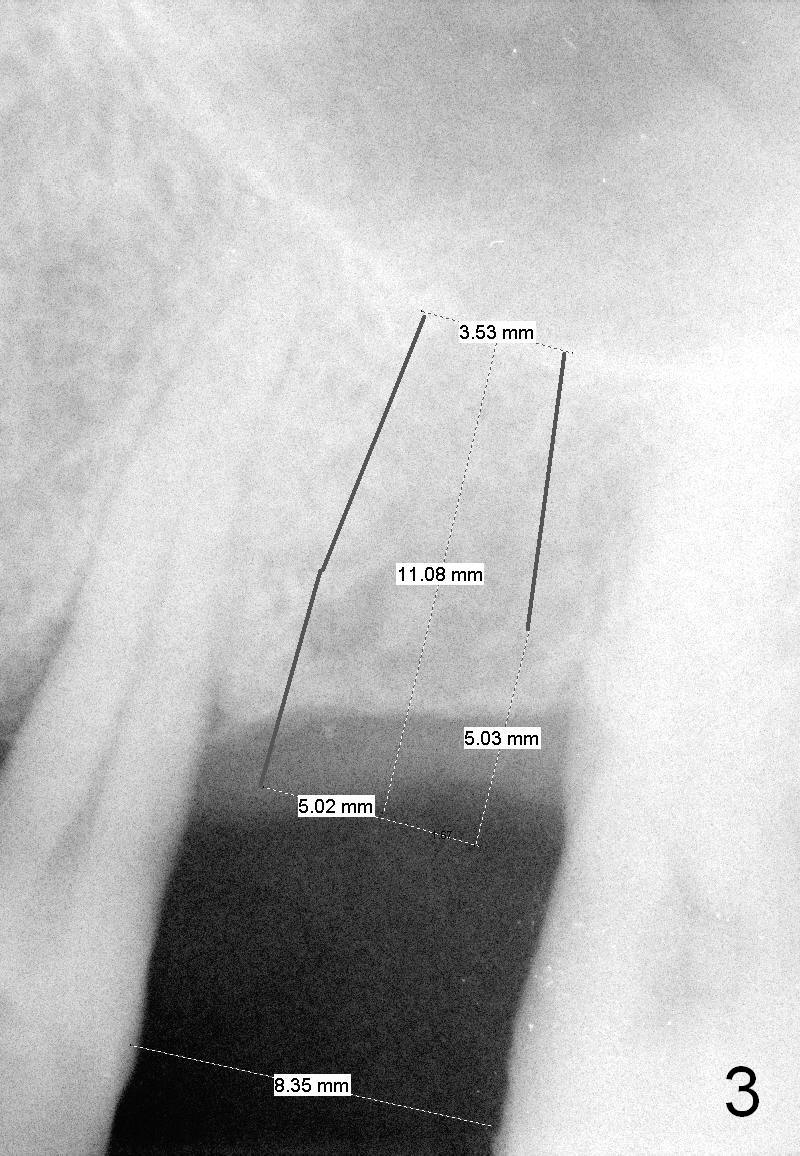

A 58-year-old man has multiple missing teeth including #14; the remaining teeth has sign of occlusal trauma (bone loss, Fig.1 arrowheads). The mesiodistal space of #14 is 8 mm (Fig.2). It appears that a 4.5x14 mm implant is appropriate for the site with sinus lift. Scalpel will be used to initiate osteotomy and bone expansion in case the bone density turns out to be low. To prevent the sinus membrane perforation, use a shorter implant (11 mm, Fig.3).